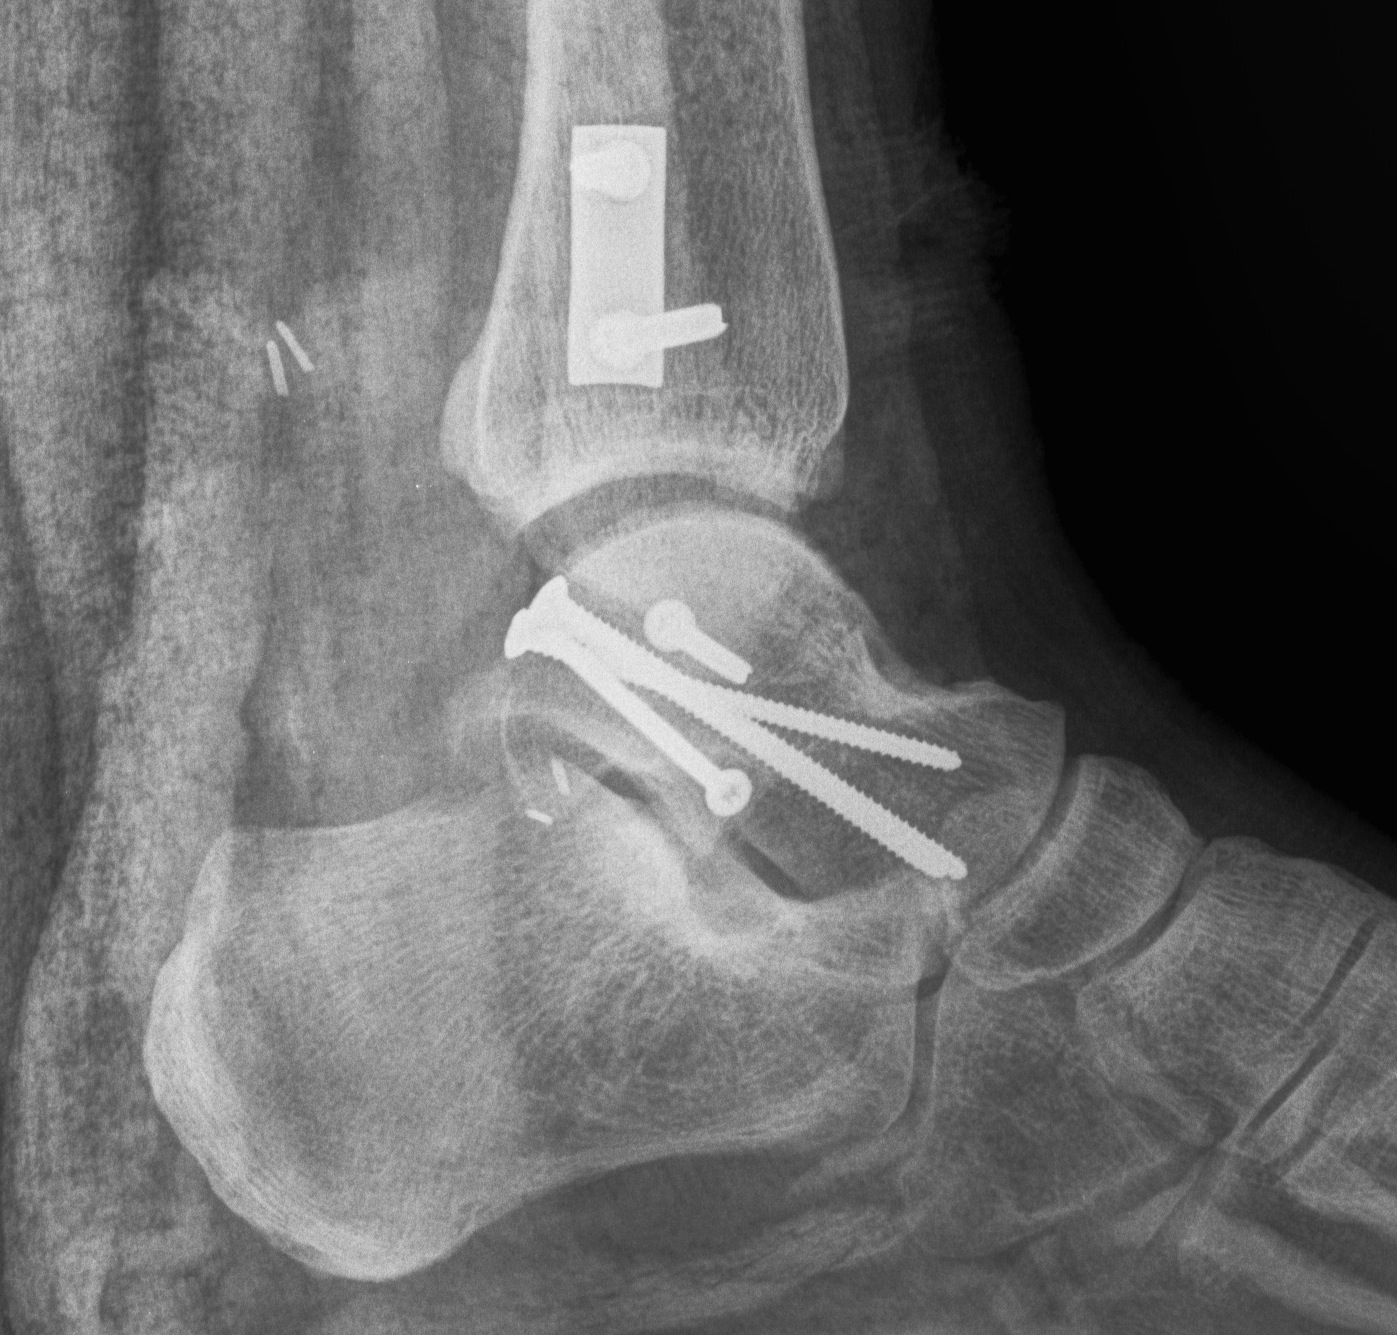

Cannulated screws

Xrays

| AP | Lateral | Canale View |

|---|---|---|

| Entry point of the screws |

Evaluate neck reduction

|

Evaluates the neck reduction |

Lateral off articular surface Medial through articular cartilage |

Depth of screws |

Beam angled 75o to foot Foot 15o pronated |

2. Antegrade (posterior to anterior) screws

- between FHL and peroneals

- entry point lateral tubercle talus

- bury to avoid posterior impingement

Antegrade screws

Plates

Options

- mini fragment plates

- anatomically contoured talar neck plates

- lateral talar neck very curved